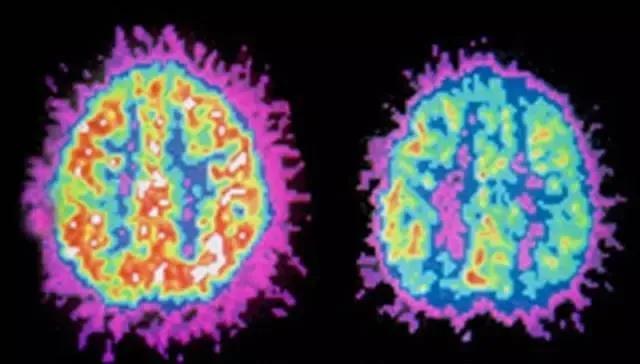

对于多动症孩子也是同样的道理,ADHD孩子的大脑结构和正常孩子是有差别的。

多动症孩子的大脑(左)VS正常孩子的大脑(右)

02.ADHD大脑和正常大脑有什么差别?

多动症(ADHD)患者五个皮层下的脑中心区域体积较小!

尤其是在青少年群体内,这种情况尤其明显。